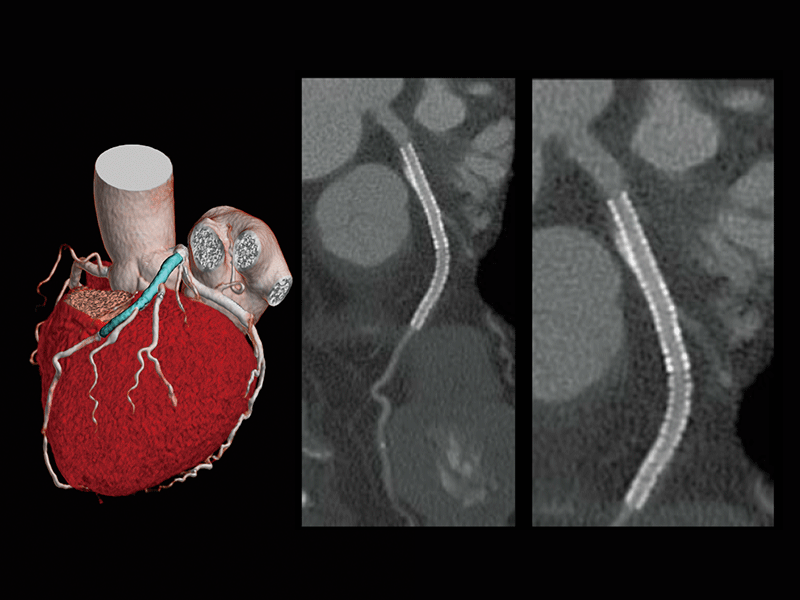

Follow-up after CABG

Follow-up after LAD stenting